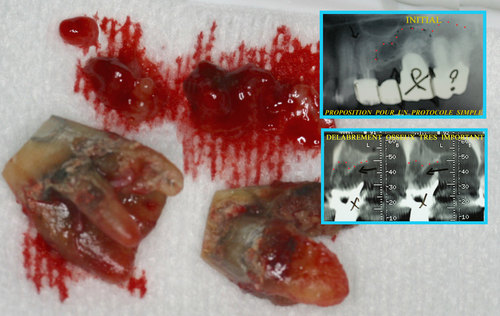

Les infections des dents provoquent des lésions osseuses avec disparition du volume osseux au fur et à mesure que l’infection se propage dans l’os des maxillaires. (fig. 29)

Fig. 29

Les infections dentaires provoquent des pertes osseuses importantes